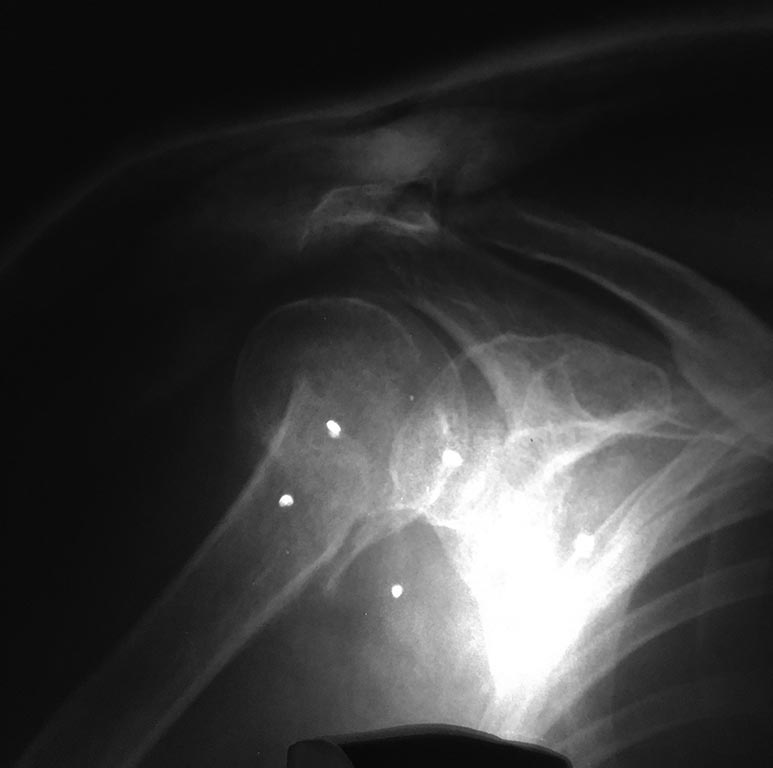

Закрытый перелом хирургической шейки левой плечевой кости со смещением. Выполнена закрытая ручная репозиция.

После 6 недель гипса доктор сообщил об образовании ложного сустава. Бабушке 75 лет. Подскажите есть ли возможность избежать в дальнейшем болей и улучшить работоспособность руки.

Похоже на несращение. Хотя для уточнения надо и посмотреть пацинтку, и сделать снимки в других проекциях. Если нет сращения, и есть болезненные проявления - лучше сделать остеосинтез. Можно обратиться в институт травматологии, к нам в отделение (Московская, 12) с 9 до 14 в рабочие дни. Паспорт, полис и снимки захватите.